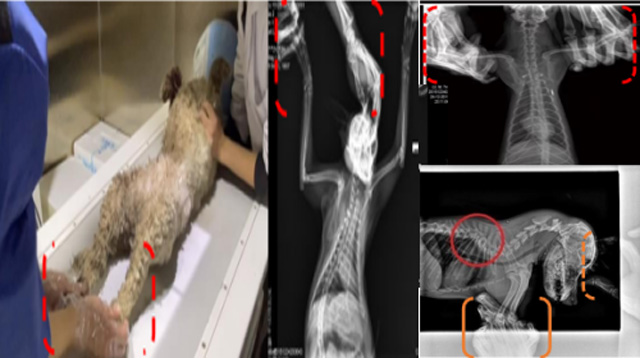

现在宠物医疗设备得到高速发展,现在有越来越多的宠物诊疗机构配置X射线装置如宠物DR。宠物骨折或者有其他疾病不能通过直观看出来的。宠物诊所医生都会使用宠物DR来做辅助检查。但是有时候宠物医生没有加强防护,就在宠物DR室给宠物拍X片做检查。这样也是会受到X射线的辐射。因为X射线上岗是属于职业病危害岗位。长期的辐射会对人体造成一定的危害。宠物医生也需要接受X射线照射的上岗前都必须进行放射工作人员的职业健康体检。体检不合格的话是不能担任放射工作的。未经上岗前职业健康体检的劳动者从事接触职业病危害作业的行为,已经违反了《中华人民共和国职业病防治法》第三十五条规定,依据《中华人民共和国职业病防治法》第七十五条规定,需要进行整改罚款。开展宠物放射诊疗活动,在日常工作中,对本机构的X射线危害的职业病防治,需要知道并做到以下内容:

建造X射线机房时寻找专业防护施工队伍,对机房四方及上下方墙体进行屏蔽防护,尽可能隔室操作,使用铅防护门并安装工作指示灯张贴警示标识进行提醒。放射工作人员跟宠物主进入DR室需要穿戴铅衣、铅帽、铅手套等做好防护,减少X射线的辐射。避免暴露在照射范围中。宠物医生上岗前、在岗时、离开岗位时候的职业健康体检。如果检查异常就需要复查跟调离放射岗位。实施个人剂量监测和防护知识培训。并在劳动合同中向放射工作人员告知X射线危害相关内容。定期委托职业技术服务机构对机房防护、放射诊疗设备性能进行检测。不能忽略了对人的保护。